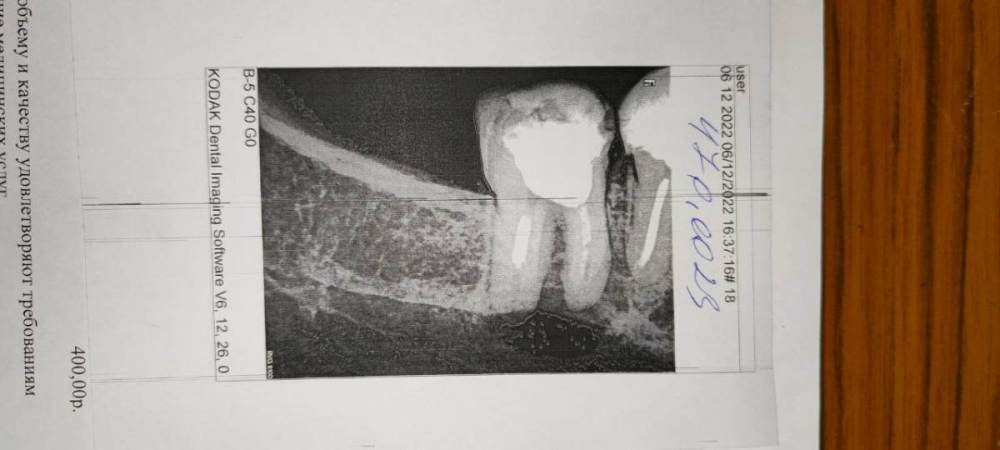

Oleg Sergeev Опубликовано 6 декабря, 2022 Поделиться Опубликовано 6 декабря, 2022 Добрый день. Нижние семерка правая и пятерка левая. Реально ли вылечить эти зубы с кистами (перепломбировывание каналов, убор кист) ... или надо только удалять? В городской п-ке сказали оба под удаление. Вопрос срочный, боимся флюса) Спасибо. Ссылка на комментарий

DoctorT Опубликовано 7 декабря, 2022 Поделиться Опубликовано 7 декабря, 2022 (изменено) Пятый точно можно. Семерка скорее можно чем нет. Для уточнения нужен более информативный снимок КЛКТ (3D))))) Изменено 7 декабря, 2022 пользователем DoctorT 1 2 Ссылка на комментарий

Pavel-Pskov Опубликовано 8 декабря, 2022 Поделиться Опубликовано 8 декабря, 2022 На семерке может быти микротрещтна в районе бифуркации, по этому снимку сложно сказать. 1 Ссылка на комментарий